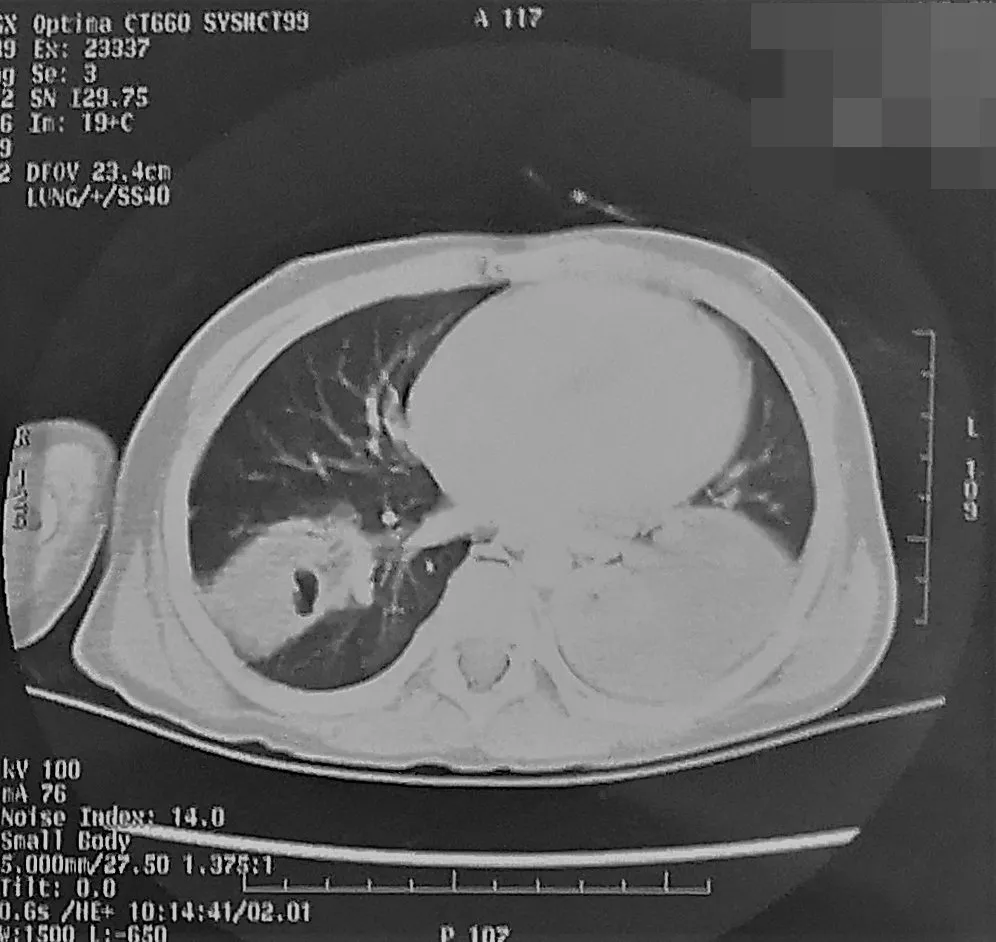

小安第一次(2019.5.13)入院时胸部CT:大片实变、胸腔积液

原来,在小安发热的最初12天里,家人认为“感冒发烧”对于身体棒棒的小安来说只是个“小毛病”,因此一直用退烧药和“中药消炎药”为小安在家治疗,但随着小安的体温升到了40℃,呼吸也越来越费劲,精神状态萎靡不振,家人才到村里诊所为其治疗。两天后,因治疗效果不好转到当地医院治疗,第一次检查就发现肺内的炎症较重,胸部CT提示双肺大片肺炎和左侧胸腔积液,给予抗感染治疗5天后,小安仍然高热不退,胸部CT提示病变继续恶化。焦急的家人将小安连夜转运到首儿所急诊,因“发热伴咳嗽19天”立即收治到了呼吸内科病房。